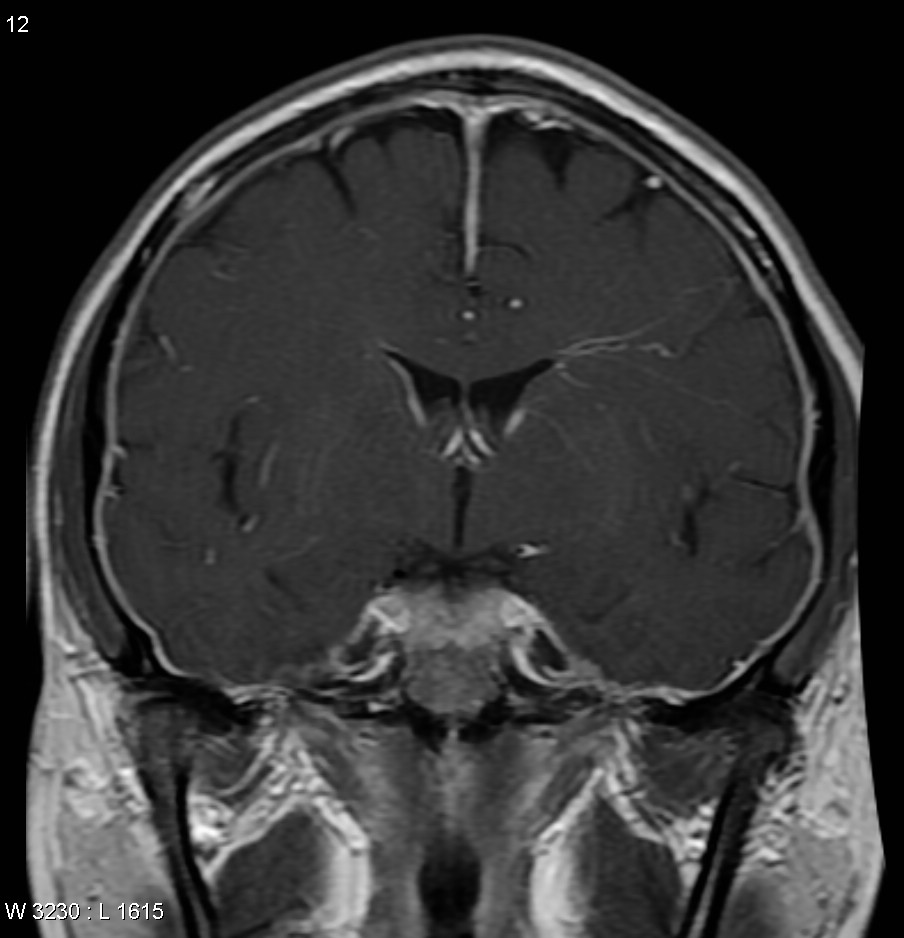

Внутричерепная гипотензия: КТ-исследования и их интерпретация